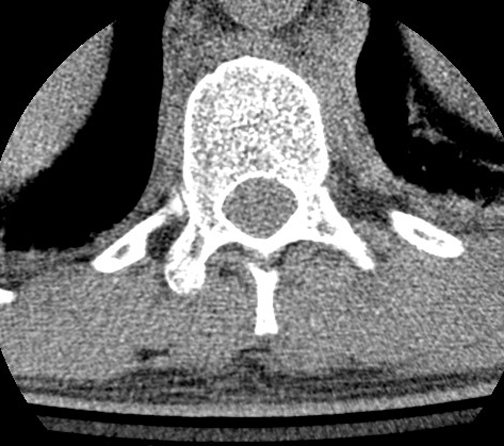

Identify the structures seen. Click the image for labeling.